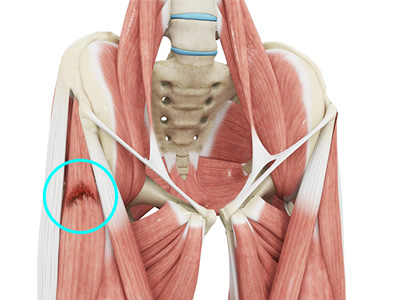

- Gluteals: These are the muscles that form the buttocks. There are three muscles (gluteus minimus, gluteus maximus, and gluteus medius) that attach to the back of the pelvis and insert into the greater trochanter of the femur.

- Hamstring muscles: These begin at the bottom of the pelvis and run down the back of the thigh. Because they cross the back of the hip joint, they help in extension of the hip by pulling it backward.